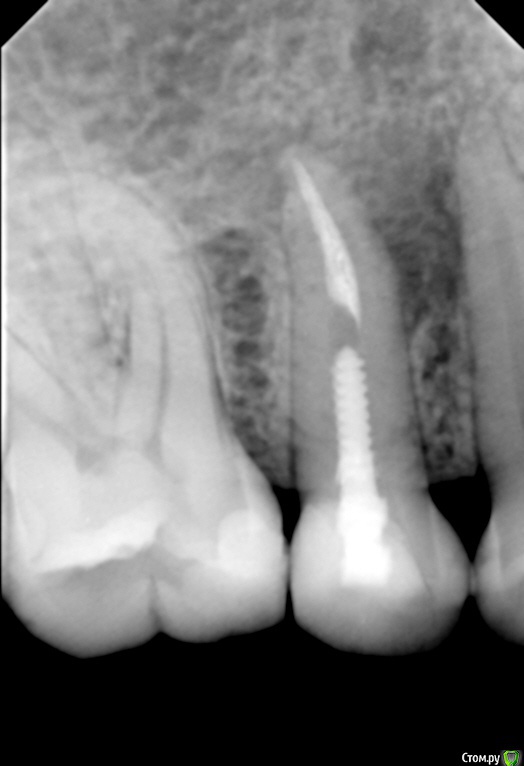

Kolchanov Опубликовано 13 июня, 2016 Автор Поделиться Опубликовано 13 июня, 2016 (изменено) Что-то не могу понять, есть процесс или нет? Рисунок костной ткани какой-то... Изменено 13 июня, 2016 пользователем Kolchanov Ссылка на комментарий

vse32 Опубликовано 13 июня, 2016 Поделиться Опубликовано 13 июня, 2016 Что-то не могу понять, есть процесс или нет? Рисунок костной ткани какой-то...45.jpgЯ перидонтальной щели не вижу. Есть желание предположить, что там что-то не совсем как видится. А может просто снимок плохой.Есть сомнения - переделайте снимок с увеличением экспозиции. Ссылка на комментарий

Л Ю С Я Опубликовано 14 июня, 2016 Поделиться Опубликовано 14 июня, 2016 Что-то не могу понять, есть процесс или нет? Рисунок костной ткани какой-то..45.jpgВот для этого нам и нужна КЛКТ. Там точно покажет. Но я уверена, что процесс есть , процентов на 90 Ссылка на комментарий